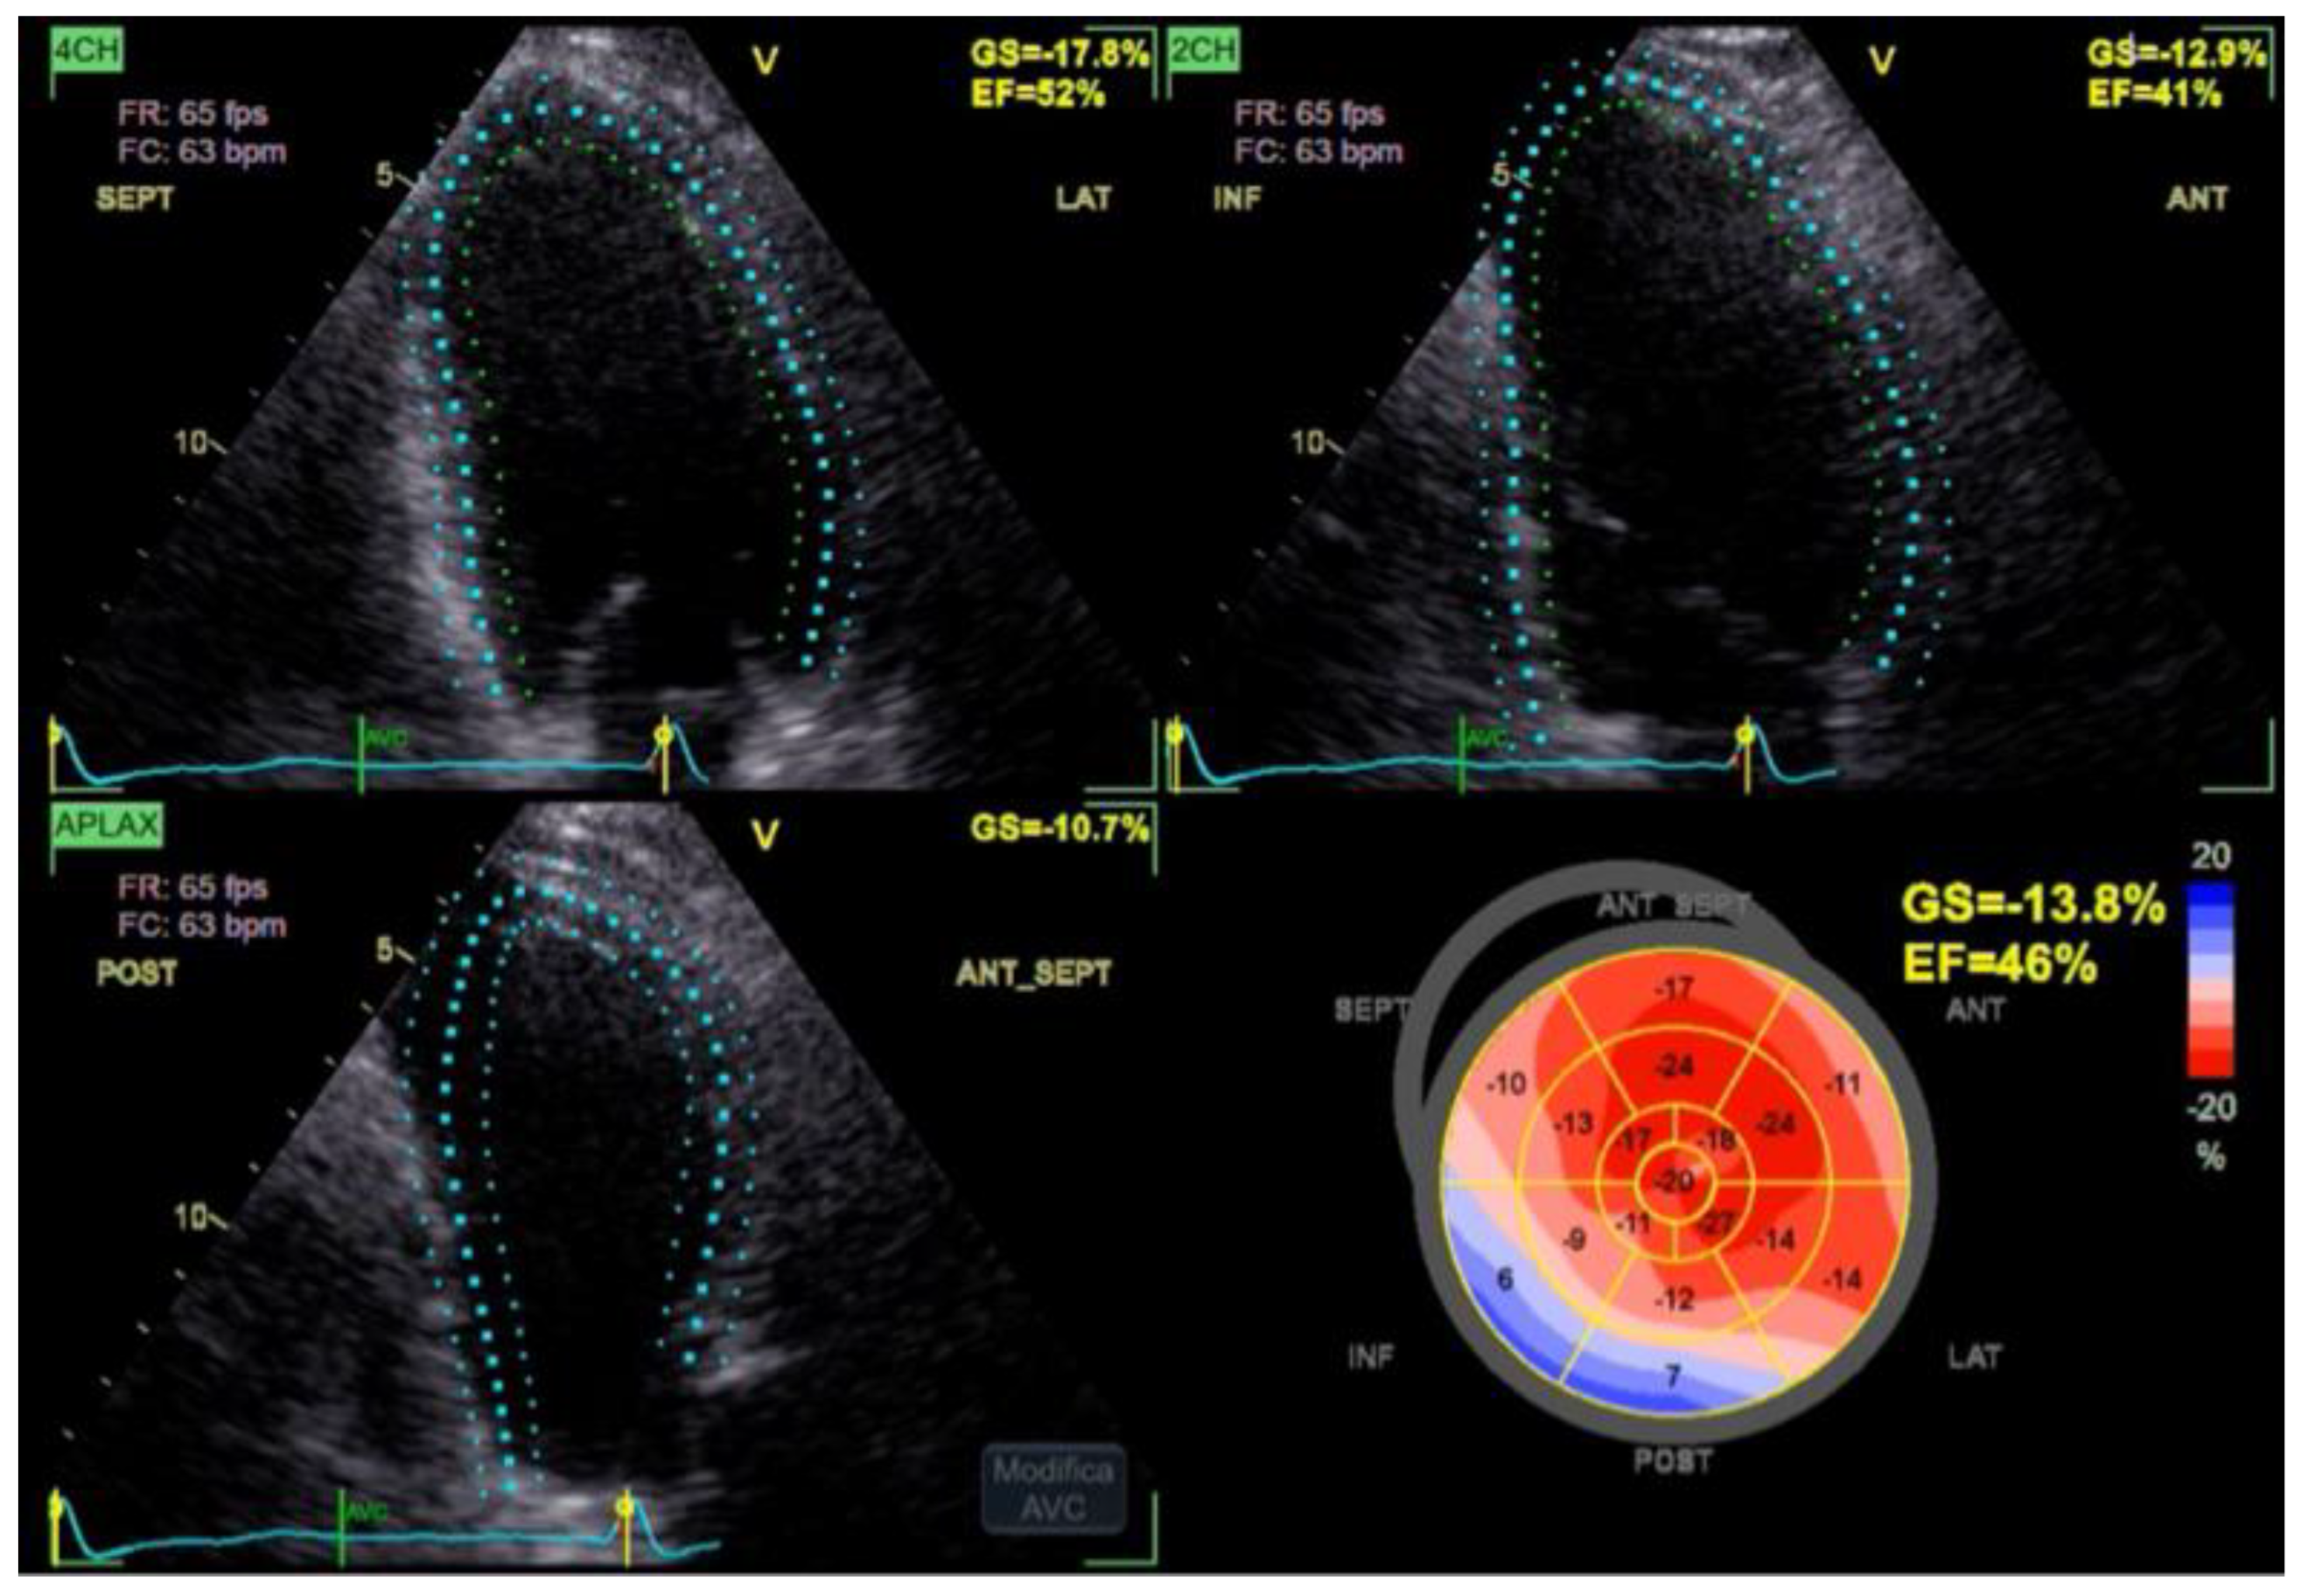

The Global Longitudinal Strain (GLS) was mildly reduced at –13.8%, reflecting the already known impairment in regional function but showing no pattern suggestive of new ischemia (Figure 2).

Figure 2. Transthoracic echocardiogram demonstrating preserved anterior wall motion, an inferior akinetic segment consistent with prior myocardial infarction, and a left ventricular ejection fraction of 46% by Simpson biplane; global longitudinal strain is mildly reduced without evidence of new regional wall motion abnormalities.

The Simpson biplane left ventricular ejection fraction was 46%, consistent with mild systolic dysfunction. The anterior wall exhibited normal thickening and contractile motion, while the inferior wall showed akinesia and fibrosis, in keeping with the patient’s known prior myocardial infarction. Importantly, no new regional wall motion abnormalities were detected.